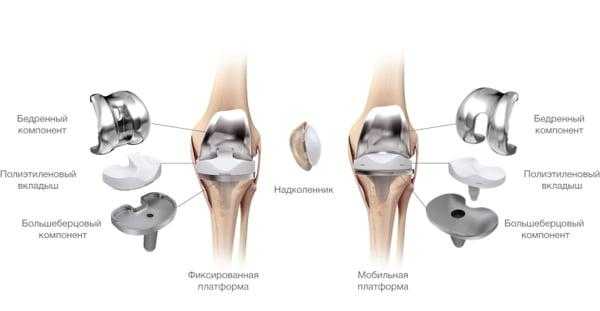

Какие бывают эндопротезы?

Протезные системы бывают с подвижной или неподвижной платформой, а также предусматривающие сохранение или удаление задней крестообразной связки. Различаются по виду фиксации, она может быть цементной, бесцементной и комбинированной.

- Подвижные и неподвижные платформы. Большинству пациентов ставят имплантат с амортизирующим вкладышем, который плотно связан с большеберцовым элементом, то есть изделия с неподвижной платформой. Наличие же мобильного вкладыша внутри металлического большеберцового компонента требует хорошего состояния мышечной системы и капсульно-связочного аппарата, в противном случае может произойти смещение протеза.

Имплантант позволяет осуществлять движения в двух плоскостях.

Самый распространенный тип импланта коленного сустава.

Типы протезов и связанные с ними методики

Вы уже знаете, что бывает полное и частичное эндопротезирование коленного сустава, где в первом случае лечение подразумевает полноценную замену суставных поверхностей, а во втором - имплантацию поврежденного участка одного из мыщелков. Соответственно, протезы классифицируются на тотальные, одномыщелковые и ревизионные для замены импланта.